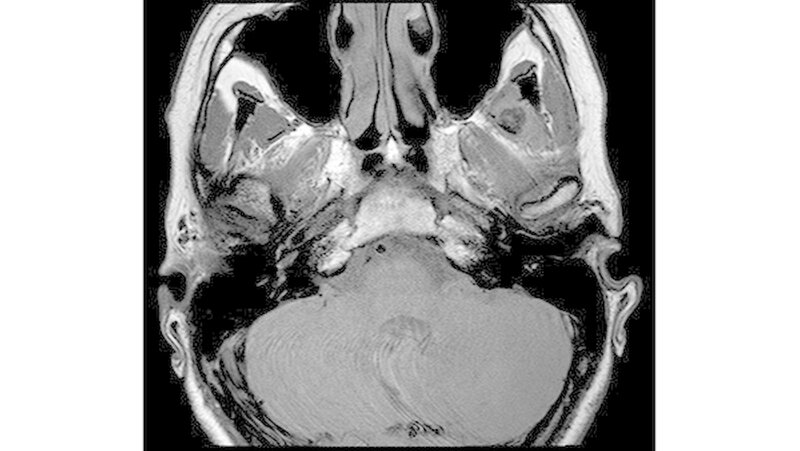

Das neun Tage später durchgeführte MRT zeigte keinen Anhalt für eine Läsion des Diskuskomplexes beidseits. Es wurde jedoch eine umschriebene, teils T2-hyperintense sowie kräftig randständig kontrastmittelaufnehmende Läsion im M. pterygoideus medialis links (axial bis zirka 1,0 cm) angrenzend an den Processus muscularis vereinbar mit einem kleinen intramuskulären Abszess beschrieben (Abbildungen 3 a und b).

Des Weiteren erschien der M. pterygoideus medialis links in seinem ganzen Verlauf ödematös verändert, jedoch ohne Anhalt für eine Beteiligung der umliegenden Strukturen wie dem M. pterygoideus lateralis.